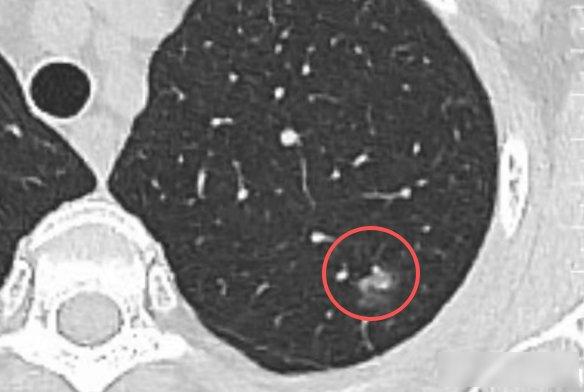

一、体检发现肺结节

很多人体检时都会查出小结节、微小结节。请记住一个关键标准:只要结节直径小于 1 公分,特别是小于 5 毫米的,超过 90% 都是良性的。

我们的肺就像身体的过滤器,每天吸入空气、呼出二氧化碳,难免会接触灰尘、细菌、病毒等微生物,这些物质进入肺部后,就会留下类似结节的痕迹。

这种情况通常不需要过度治疗或手术,关键是找专业医生判断性质。若医生评估为良性,每年体检复查、持续观察即可。